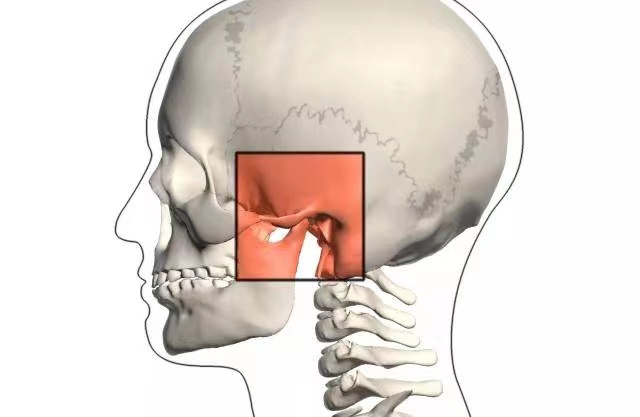

颞下颌关节(temporomandibular joint,TMJ)是铰链关节,由下颌骨髁突(condyle of mandible)与颞骨关节窝形成,属于纤维软骨关节,具有关节囊、关节盘和滑膜。颞下颌关节紊乱(TMD),也可以视为颞下颌关节结构或功能改变造成的一种急性或慢性疼痛疾病。